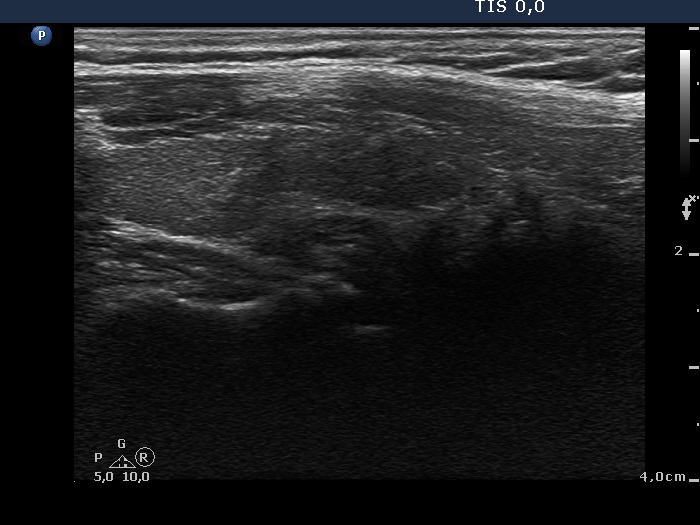

Ultrasonography: the right thyroid was echonormal while the left lobe contained moderately hypoechogenic areas with a 50% echogenicity index. There was a hypoechogenic mass lower and lateral to the right thyroid. The lesion did not present a regular hilum.